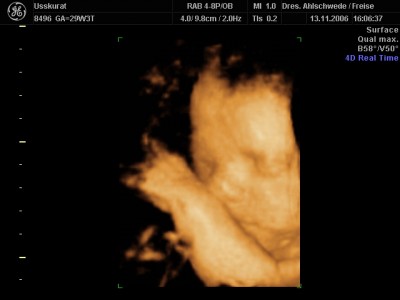

Aufgrund meines Diabetes kann Makrosomie beim Kind entstehen, dass heisst, das Kind wächst schneller als seine Organe. Unsere Lieselotte ist nun an der oberen Grenze, sie ist groß und schwer.... Knapp 42 cm und 2000 g.....

Jetzt muss ich in 2 Wochen wieder hin, vielleicht hatte sie nur gerade einen mächtigen Schub gemacht und beim nächsten Mal pendelt es sich wieder ein. CTG war gut, das Herz blubberte lustig vor sich hin. :wink: Meine FÄ meinte nur, den 26.01. werden wir vielleicht nicht als Termin halten können, im Zweifelsfall wird sie früher geholt, muss man mal abwarten.... :-?

Heute konnte man leider nur eine Hand und das Ohr besonders gut erkennen, stell Euch mal ein Bild vom letzten Mal rein, ist ja auch noch ganz frisch. :D

131106_3.JPG

Wow,Claerchen,ist das ein schööönes Bild! :dance: :dance: :dance: Ich bin ja immer wieder begeistert,wie deutlich das Alles heutzutage ist! :prima: Sowas gab's zu meiner Zeit ja nicht..schluchz :cry: .

Claerchen, davon hab ich auch schon gehört,dass Babys von Diabetiker schon größer werden können.. :grübel: Aber es könnte doch auch genau sogut sein,dass Lieselottchen einfach nur ein großes Kind ist..schließlich liegt sie ja in der Norm! :jaja: ...Sie ist einfach ein strammes Mädel!! :dance: Und das Bild fasziniert mich echt total...zu süüüüüüßßßß..will auch haben.. :cry: